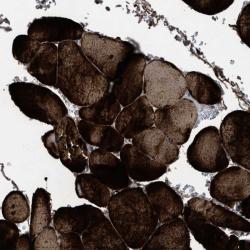

Supportive validation

- Experimental details

- Immunohistochemical staining of human skeletal muscle shows strong positivity.

- Validation comment

- Two independent antibodies targeting one protein yielding similar staining patterns. Staining pattern consistent with experimental and/or bioinformatic data.